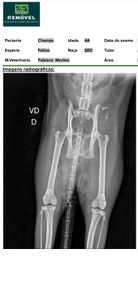

Ele precisa fazer inclusive sessões de fisioterapia URGENTEMENTE para poder recuperar o movimento das patas traseiras. Já que sofreu três fraturas pélvicas. Tenho todos os laudos médicos do Champs, inclusive o raio x que mostra suas fraturas que ele sofreu devido ao acidente. Ele precisa de medicamentos para aliviar a dor, fraldas higiênicas, rações úmidas (devido à falta de apetite por conta das dores) e de sessões de fisioterapia.